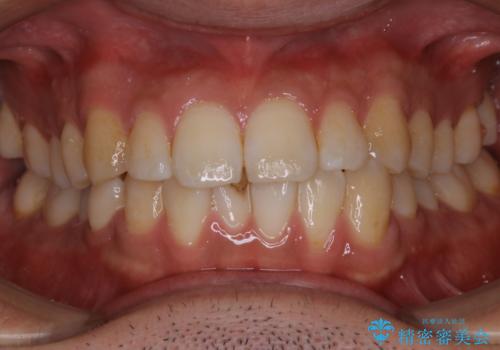

- コーヒーを毎日飲むので、どうしても着色がついてしまう。前歯の目立つ着色をきれいにとってほしいとのことでした。

PMTC60分コースを行いました。

PMTCは、歯に付着した汚れを除去していくため、着色が気になる場合にも行うことができます。ご自身でのセルフケアだけで着色を落とそうとすると、逆に歯を傷つけてしまったり、精密に汚れを除去できないこともあります。また、日常生活で着色しやすい飲食物を避けたりすることはストレスに感じてしまったり、あまり現実的ではありません。